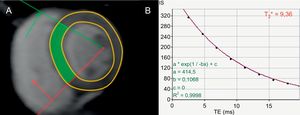

Relaxometría T2*: hierroLos depósitos de hierro en el miocardio son arritmógenos, aunque el mecanismo específico aún no está claro13,14. El hierro es paramagnético, por lo que influye en el tiempo de relajación T2* alterando la homogeneidad del campo magnético y provocando el desfase de los espines de los protones, con o que se acorta el tiempo T2*. Las secuencias eco de gradiente multieco en apnea sirven para establecer una curva de relajación T2* con una serie de imágenes a tiempos eco cada vez mayores15. A continuación, se ajusta una función exponencial a los puntos de datos según la fórmula siguiente: y=Ke–TE/T2*, donde y es la intensidad de señal, K es una constante, TE es el tiempo eco y T2* el tiempo de relajación T2*, que refleja la cantidad de hierro depositado en el miocardio15,16.

Evaluación del riesgo de muerte súbita cardiaca en la miocardiopatía por sobrecarga de hierro. A: corte del ventrículo izquierdo de eje corto a nivel de los músculos papilares, adquirido con una secuencia en T2*. B: curva de relajación en T2*, que traza la intensidad de señal frente al tiempo de eco desde la región septal de interés (indicada en verde en la imagen A), que muestra un tiempo de relajación T2* reducido, de 9,36 ms, debido a la sobrecarga de hierro miocárdica; un T2* <20 ms se relaciona con arritmias ventriculares93. Adaptado con autorización de Gupta et al.94. Esta figura se muestra a todo color solo en la versión electrónica del artículo.